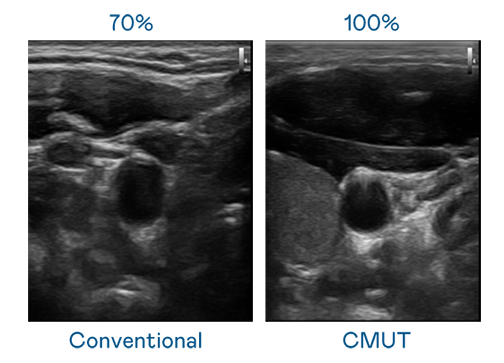

CMUT 技术是一种用电容式微机电元件来产生超音波讯号的技术。与传统 PZT 压电式技术相比,CMUT 频宽增加 30%,更宽频的超音波讯号让影像解析度大幅提升,是实现高影像品质医疗超音波扫描、促进精准医疗发展的关键技术。

超音波影像的解析度高低,首先取决于探头能发出的讯号频宽。红桃国际 CMUT 可提供高清晰的超音波讯号,提供高频宽、高灵敏度、影像纹理细节更高的超音波影像,协助医护人员缩短影像判读时间及利用精准的医疗影像进行诊断。